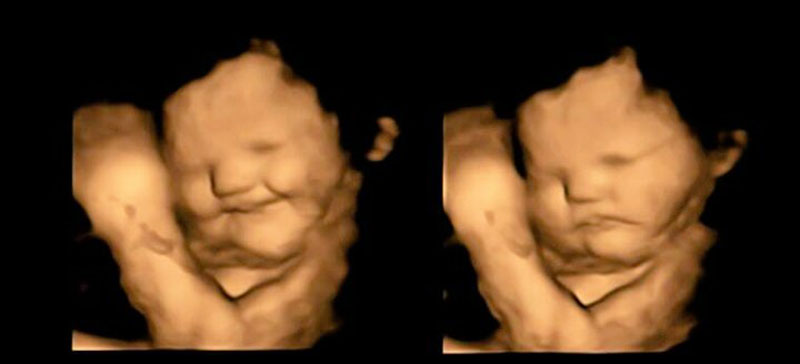

Εάν η γεύση του kale ή της λαχανίδας όπως ονομάζεται στα ελληνικά σας "ξινίζει", να γνωρίζετε πως δεν είστε μόνοι, καθώς ερευνητές παρατήρησαν πως τα έμβρυα αποκτούν μία μάλλον κλαμμένη έκφραση, όταν οι μητέρες τους καταναλώνουν το συγκεκριμένο λαχανικό.